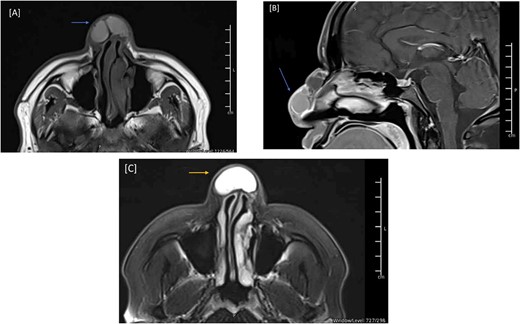

During the physical examination, there was a large globular swelling on the dorsum of the nose extending to both sides with erythema but without warmth (Fig. 1). The patient’s breathing was not affected. A magnetic resonance imaging (MRI) of the head with contrast showed a multiloculated midline cystic lesion on the dorsum of the nose, with some parts showing high proteinaceous content. No connection to the cranial cavity was observed (Fig. 2). These features suggest a dermoid cyst. The size of the lesion is depicted in Supplementary Fig. S1.

MRI of the head, and paranasal sinuses (Pre-Op). (A) There is a lobulated multilocular cystic lesion seen at the dorsum of the nose, some of the cysts are showing bright signal intensity in T1 (arrow) and T2/FLAIR (C) (arrow) representing high proteinaceous content. No connection to the cranial cavity, features are likely presenting dermoid cyst. (B) The lesion shows peripheral postcontrast enhancement. No diffusion restriction.